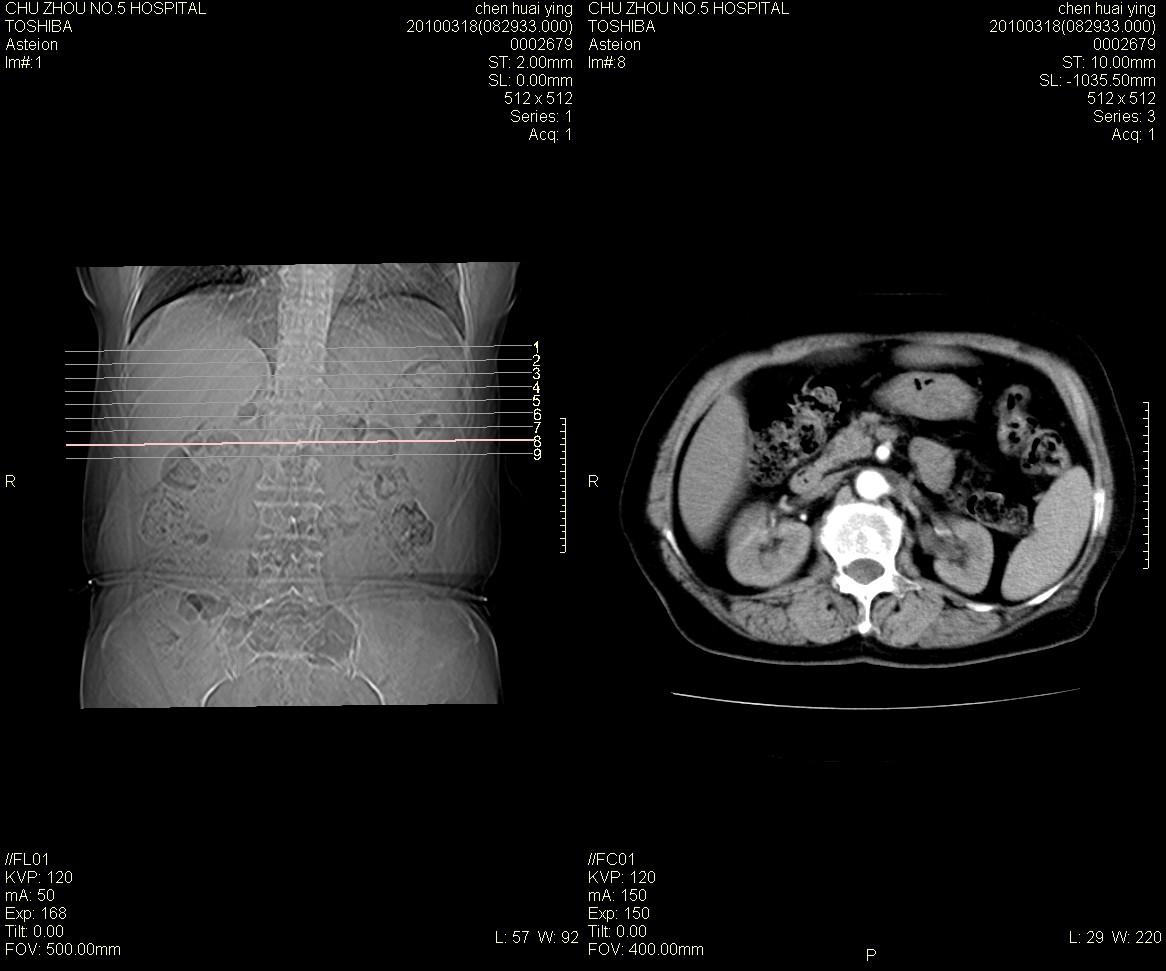

标题: CT25148 肾上腺增强

ct25148增强图片

动脉期太早了,扫的有点低。考虑良性占位右侧肾上腺嗜铬细胞瘤并坏死囊变可能性大,神经鞘瘤不排除。

考虑双侧肾上腺肿瘤性病变。